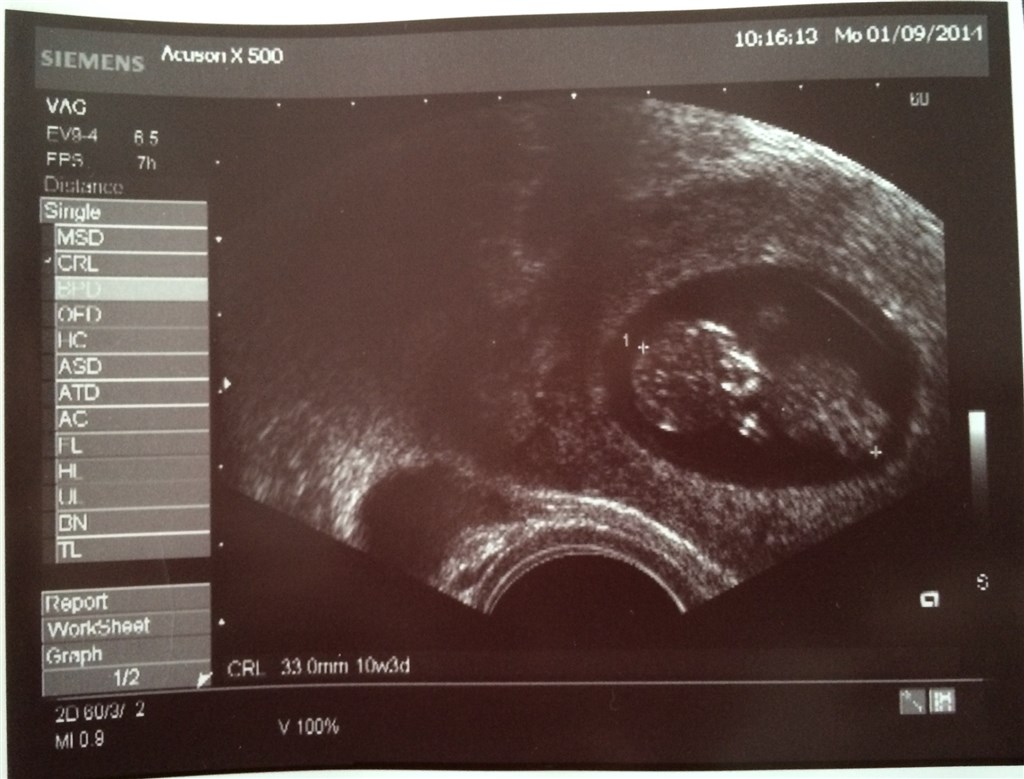

har været til 3 skanninger allerede, de to første var meget tidligt (7+2 & 8+2) , men der var hjerteblink begge gange! Og i dag har vi været til scanning igen er 10+2 og bebs baskede fint med både arme og ben, det var så rørende og livsbekræftende at se!

I får også lige billeder fra scanning i uge 8+2 og 10+2

Vedhæftede fotos (klik for at se i fuld størrelse)